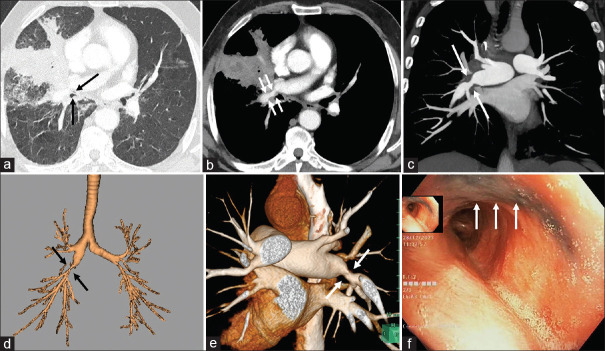

Bronchial anthracofibrosis beyond bronchial involvement causing pulmonary artery stenosis.

超出支气管范围的支气管炭疽性纤维化,引起肺动脉狭窄。